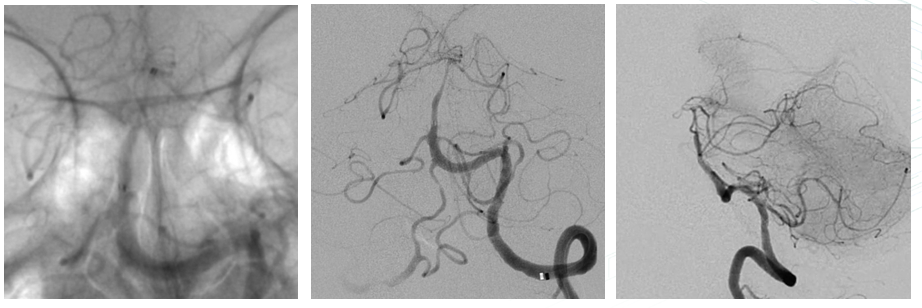

Preoperative Angiography

Preoperative MRI: Distal basilar artery occlusion.

DSA before treatment: Bilateral posterior communicating arteries were patent; posterior cerebral arteries visualized clearly.

Left vertebral artery was dominant; distal basilar artery was hypoplastic. Poor visualization of superior cerebellar artery and thalamoperforating branches.

After deployment of Zenith Stent Retriever, distal vessel branches reappeared. Post-thrombectomy angiography showed restored antegrade flow, but with residual severe stenosis.

3D DSA evaluation: Poor hemodynamic compensation at the lesion segment. Balloon dilation was considered risky due to inaccessibility and high risk of vessel rupture. Microcatheter was re-advanced across the stenosis. A 3.0 mm × 15 mm non-tapered intracranial stent was deployed slowly.

The stent expanded and apposed well, with good in-stent flow and improved visualization of distal branches.

15-minute follow-up angiography showed stable in-stent flow in the basilar artery